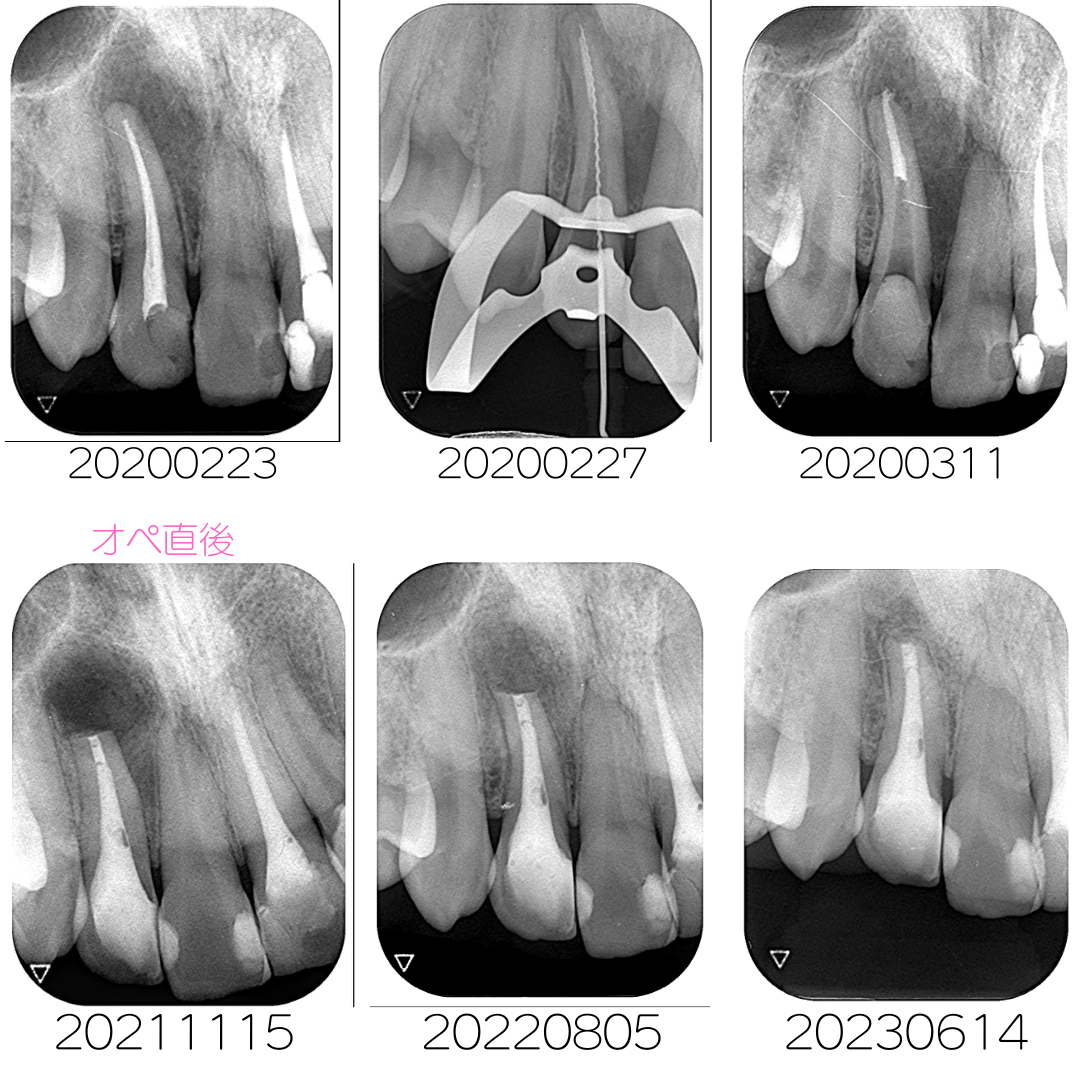

術前から術後3年までの経過(時系列)

治癒の経過がよく分かると思います。術後3年経過していますが、再発することなく安定しています。

術前術後の写真

まずは結果からご覧ください。歯根にある大きな病変が小さくなっていることがわかります。